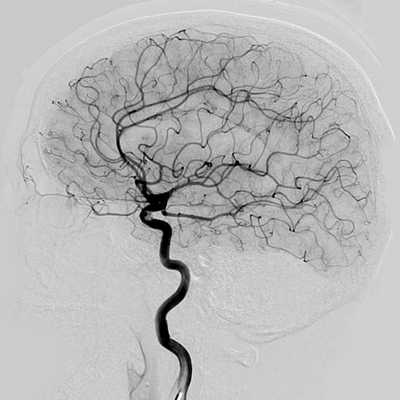

КТ или МРТ ангиография сосудов головного мозга - что лучше

КТ (компьютерная томография) и МРТ (магнитно-резонансная томография) сосудов головного мозга применяются для диагностики патологий сосудистой сети головы и шеи. Альтернативное название этого исследования - МР или КТ-ангиография головного мозга. Что лучше выбрать - МРТ или КТ сосудов головного мозга? Ответ на это вопрос мы постараемся дать в этой статье.

Что такое МРТ и КТ сосудов головного мозга

Понятие КТ или МР-ангиография часто используется в медицинской литературе и практике как собирательный термин для любого обследования сосудов с помощью томографа. В МРТ центрах МР-ангиографией принято называть магнитно-резонансное исследование артерий, альтернативное название МР- артериография или МРТ сосудов головного мозга. Это обследование не включает сканирование вен головы. Для этого проводится отдельное исследование - МР-венография. Отличие МР-ангиографии от МР-венографии заключается в диагностическом фокусе и программном обеспечении. МРА визуализирует артериальную сосудистую систему, а МР-венография (МРВ) показывает венозное русло.

Отличия МРТ и КТ ангиографии от классической ангиографии

МРТ и КТ ангиографию не следует путать с прямой ангиографией. Классическая ангиография - это технологически простой метод исследования. Он появился в 1927 году, когда португальский невролог доктор Мониц провел первое ангиографическое исследование с введением контрастного вещества. Долгое время этот метод оставался золотым стандартом обследования сосудов головы, сердца, позвоночника, шеи, нижних конечностей и брюшной аорты. Основным недостатком данного вида ангиографии является необходимость сделать механический прокол сосудов (сонной или бедренной артерии), чтобы ввести контрастное вещество и обследующее устройство. Прямая АГ- это, в конечном счете, инвазивная манипуляция, требующая госпитализации и имеющая определенный риск осложнений. Кроме того, классическая ангиография дает возможность делать ангиограммы только в прямой или боковой проекции.

У прямой агиографии есть и диагностические ограничения. С ее помощью врач может достаточно подробно рассмотреть сами сосудистые аномалии (стеноз, окклюзии), но по ней нельзя получить информацию о мальформациях артерий, тромбозах вен, характере кровоизлияния при инсульте, состоянии вещества головного мозга. Для этого потребуется КТ или МРТ сосудов головного мозга.

В чем разница между МР или КТ агиографией мозга

Принцип получения изображения - это основное принципиальное отличие МРТ и КТ сосудов головного мозга. При компьютерной агиографии используется рентген-лучи. Во время сканирования они проходят сквозь зону обследования под различными углами, а датчики аппарата оценивают скорость прохождения Х-лучей сквозь ткани различной плотности.

Работа МРТ основывается на эффекте ядерно-магнитного резонанса, при котором атомы водорода в клетках организма начинают колебательные движения, находясь под воздействием магнитного поля и радиочастотных импульсов. Этот резонанс улавливает томограф и транслирует в трехмерные изображения сосудистой сети. Поскольку кровь содержит много воды и является хорошим парамагнетиком, контрастирования для МР-агиографии в большинстве случаев не требуется.

МР-ангиография головного мозга обычно занимает в среднем 15-20 минут. Если необходимо введение контраста, продолжительность исследования доходит до 40 минут, поскольку врачу нужно по сути провести два сканирования: пре-контрастное и контрастное, а потом сравнить результаты. КТ сосудов головного мозга с контрастированием занимает 20-30 минут.